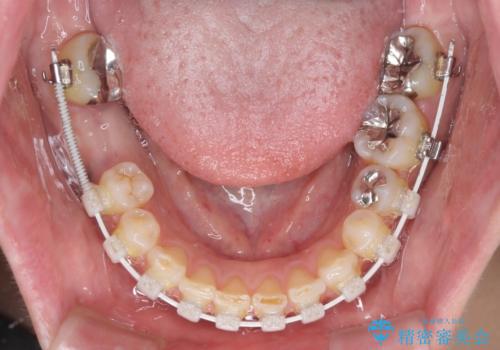

咬み合わせ改善のため、前歯の過剰歯を抜去し、ワイヤー矯正にて歯列と咬み合わせることとしました。

また、右下の抜歯が必要な奥歯は、矯正治療の途中でインプラントを埋入し、矯正治療後に上顎と合わせて補綴治療を行うこととしました。

上下非接触の咬み合わせは、舌突出癖によるところが大きく、トレーニングを行いながら治療を進めていきました。

なかなか突出癖が改善できず、過剰歯を抜歯したスペースを閉じるまでに時間がかかりました。

舌突出癖の改善は、治療期間や仕上がりに大きな影響を与えるため、しっかりとトレーニングすることが大切です。